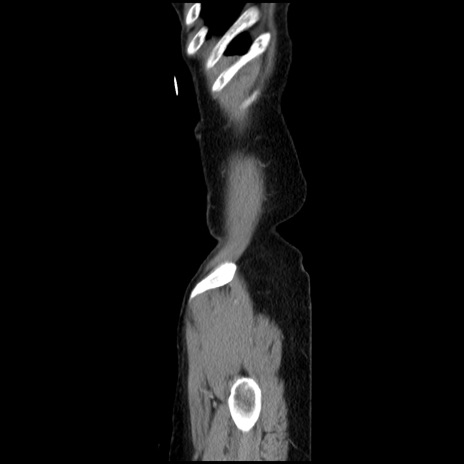

症例32(矢状断像)

【症例】40歳代 女性

【主訴】上腹部痛、嘔気・嘔吐

【現病歴】約9時間前頃から急に上腹部痛、嘔気、嘔吐が出現。改善しないため救急要請。

【既往歴】子宮頚癌(広汎子宮全摘術、放射線療法)、腸閉塞

【身体所見】腹部:平坦、軟、腸雑音亢進、上腹部を中心に腹部全体に圧痛あり。

【データ】WBC 8400、CRP 0.03